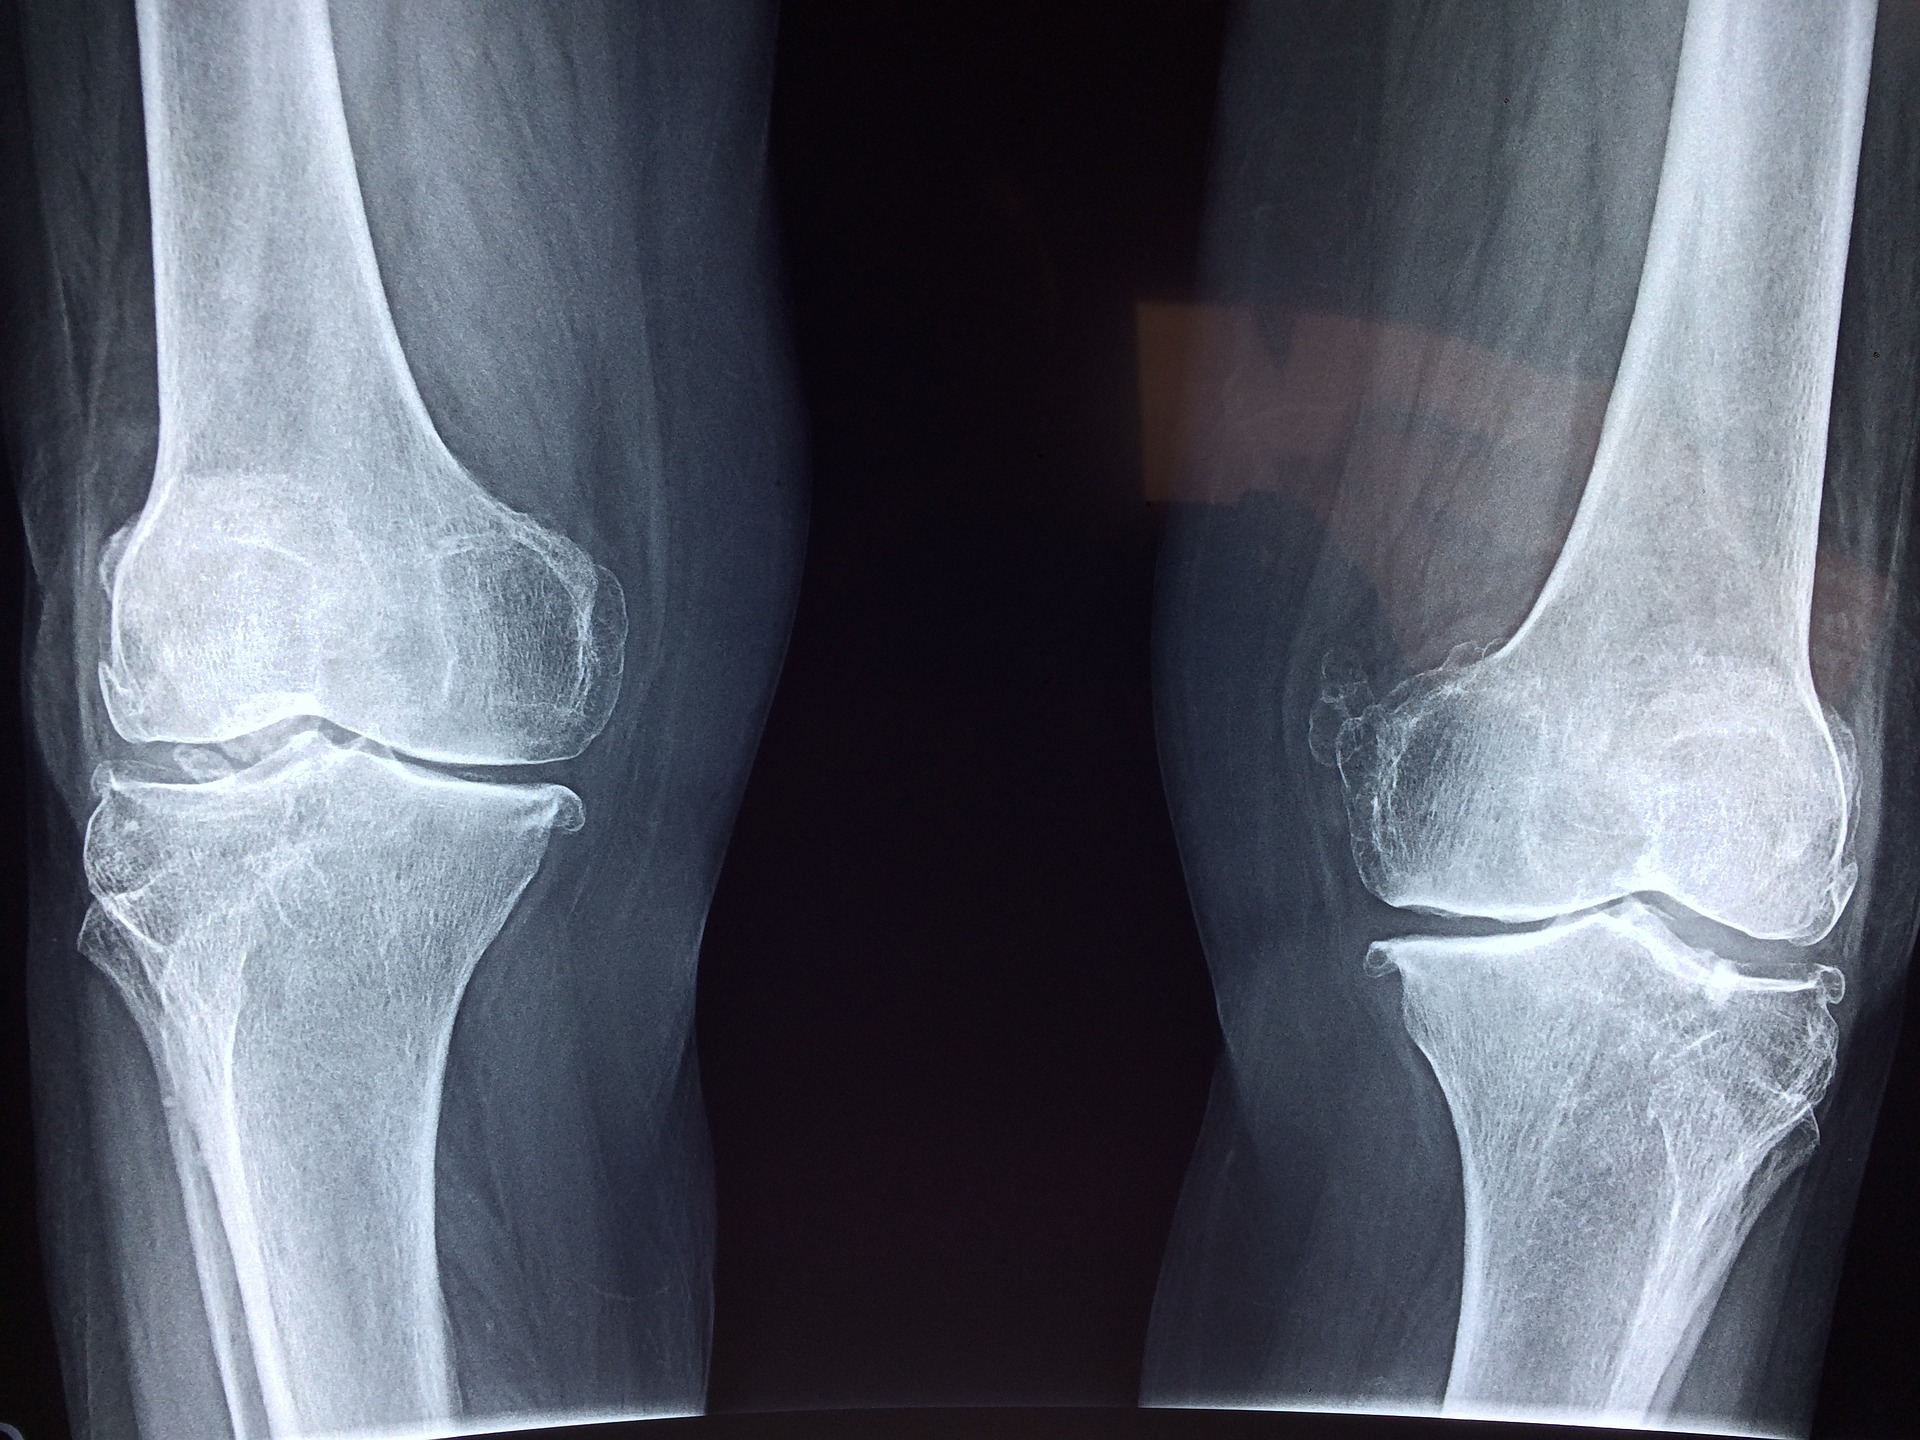

أشار الدكتور نبيل عبدالله، استشاري المفاصل وأمراض الروماتيزم بمؤسسة حمد، إلى خطورة كسور الورك المرتبطة بهشاشة العظام، موضحًا أن قسم الطوارئ في مستشفى حمد العام سجل أكثر من 100 حالة من كسور الورك خلال عام 2023. وأضاف الدكتور عبدالله أن كسور الورك يمكن أن تؤدي إلى فقدان القدرة على التعايش بصورة مستقلة، وتهدد حياة المرضى، كما تؤثر سلبًا على رفاهيتهم ورفاهية أسرهم ومقدمي الرعاية لهم. كما نوه بأن هناك أنواعًا أخرى من كسور هشاشة العظام مثل كسور العمود الفقري وكسور الساعد التي تعد أكثر شيوعًا من كسور الورك.

تعتبر هشاشة العظام حالة مرضية تتميز بضعف وترقق العظام، مما يزيد من خطر الإصابة بالكسور خاصة عند التعرض لإصابات طفيفة. تزيد نسبة الإصابة بهذا المرض لدى كبار السن والنساء، وتشمل عوامل الخطر الرئيسية العمر المتقدم، والنوع، والتاريخ العائلي للإصابة، بالإضافة إلى العادات المرتبطة بنمط الحياة مثل سوء النظام الغذائي، وقلة ممارسة التمارين الرياضية، والتدخين.